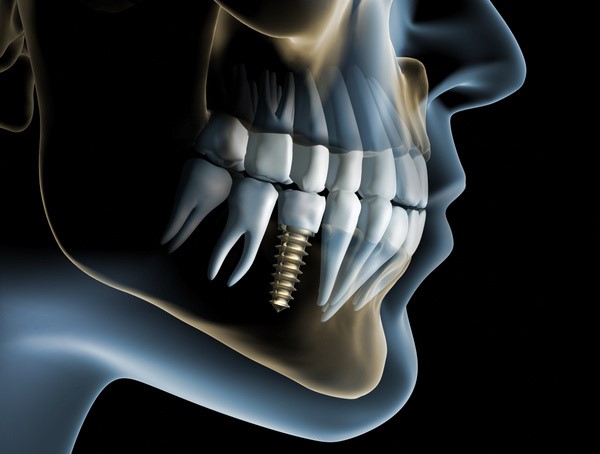

L’ implantologia computer guidata è una rivoluzionaria ed innovativa procedura che permette di progettare al computer, tramite l’utilizzo di precisi software, l’intervento di inserimento degli impianti dentali nelle ossa. Il tutto è possibile tramite un protocollo digitale che prevede prima l’acquisizione di immagini radiografiche 3D proveniente dall’esame CBCT (tac dentale) sovrapposte alle immagini 3D provenienti dalla scansione intraorale della bocca del paziente. Il progetto implantare così eseguito dal medico al pc viene poi trasferito nella bocca del paziente tramite delle dime chirurgiche che fungono da guida per il chirurgo durante l’intervento. Questa procedura rende l’intervento meno invasivo, a volte senza rendere necessari punti di sutura, utilizzando una precisione computerizzata.